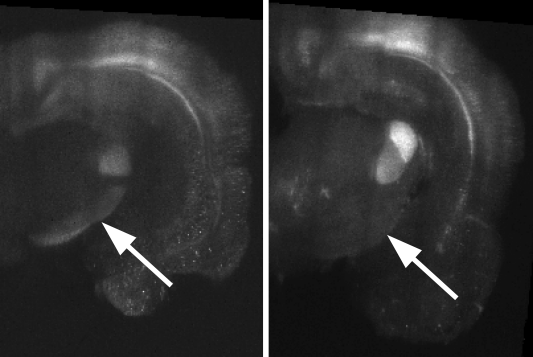

1.6 Challenges

In addition to their large size, CLARITY images present several unique challenges for image registration. In the CLARITY images of this study, a neuron’s brightness is proportional to its activity, which means that CLARITY images have a functional component. Regions which appear bright in one CLARITY brain may appear dark in another (Fig. 3a). Registration is further complicated by brain deformation introduced in the clarifying process (Fig. 3b) and missing data (Fig. 3c).